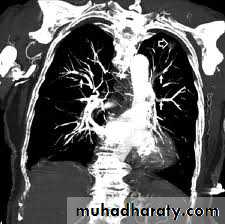

Spiral CT

CT scan and angiogram – it is comfirmative and can detect the pulmonary artery and it is branches (As contrast may be nephrotoxic, care should be taken in patients with renal impairment and the use of iodinated contrast media should be avoided in those with a history of allergy to it).